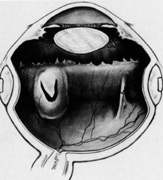

Scleral Perforation

Scleral perforation during placement of scleral sutures is a potentially disastrous complication (Fig. 40). Perforation usually is noticed at the time of suture placement and is heralded by the presentation of blood, pigment, subretinal fluid, or a combination thereof through the suture tract. If perforation is recognized, the retina should be inspected immediately with an indirect ophthalmoscope to determine the depth of the perforation. If the suture is in the choroid or subretinal space without evidence of bleeding or continuing subretinal fluid drainage, nothing additional needs to be done, and placement of remaining suture may be performed if necessary.

Fig. 40. Scleral perforation during suture placement with subretinal hemorrhage and retinal break.

If subretinal fluid is lost with continuing drainage through the suture tract, drainage is allowed to proceed while an attempt is made to maintain a constant intraocular pressure. When drainage stops, the retina is inspected to determine if drainage has been adequate. If so, any remaining necessary sutures are placed and the buckle positioned.